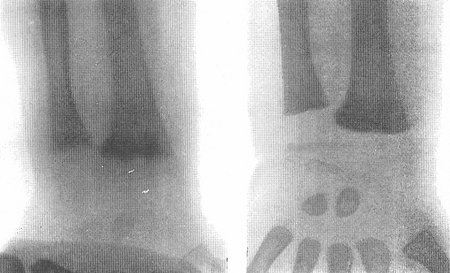

X-rays of a wrist from a child with vitamin D-deficiency rickets before (left panel) and after (right panel) treatment with vitamin D

From the collection of M.F. Holick, PhD, MD; used with permission